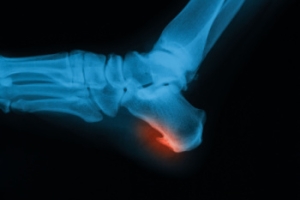

Bone spurs in the feet, also called osteophytes, form when the body produces extra calcium in response to stress, friction, or inflammation. These growths are not always painful, but they can interfere with nearby tissues and cause discomfort. Heel spurs are one of the most common types. They develop beneath the heel bone from strain on the plantar fascia or at the back of the heel due to tension from the Achilles tendon. Tarsal spurs occur in the midfoot, either on the top or bottom, and often make wearing shoes painful because of pressure against the spur. Toe joint spurs typically affect the big toe, leading to stiffness, limited motion, and pain while walking, especially when arthritis is present. A podiatrist can determine the cause of the bone spur, relieve pressure on surrounding structures, and recommend treatment. If you are experiencing foot or heel pain, it is suggested that you schedule an appointment with a podiatrist for an exam and appropriate treatment.

To figure out the cause of foot pain, podiatrists utilize several different methods. This can range from simple visual inspections and sensation tests to X-rays and MRI scans. Prior medical history, family medical history, and any recent physical traumatic events will all be taken into consideration for a proper diagnosis.